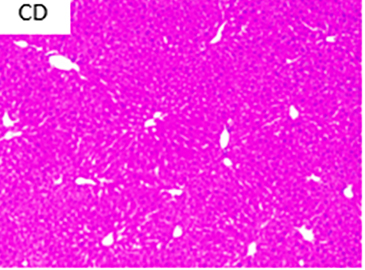

Fotografías a cortes histológicos de hígado, después de 12 semanas, parte de ensayo preclínico: CD: dieta control; HFD: dieta alta en grasa; A1: dieta alta en grasa + concentrado Omega-3 pescado; y A4: dieta alta en grasa + lípidos terapéuticos Nutri-Omics. Flechas muestran los distintos niveles de gravedad de los focos de esteatosis macro y micro vesicular después de ser sometidos a una dieta alta en grasa.